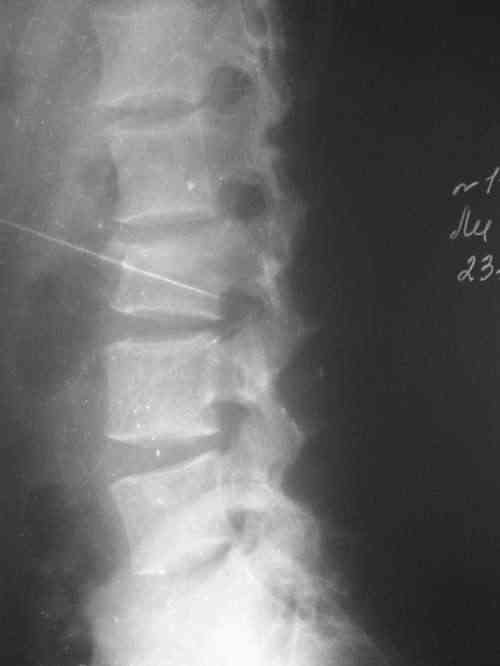

Перелом позвоночника неосложненный! А чего-й то функция тазовых органов нарушена? На взгляд - он нестабильный. По правильному следовало бы оперировать и спинку и пятки. А если не оперировать - то крутите тихонечко (можете наложить корсет по Белеру) или другой реклинирующий корсет. Хуже не

будет. С ув. А Рыков. Хабаровск.

Нарушение функции тазовых органов связано с переломом седалищной кости без смещения??? ...или это опечатка, и функция тазовых органов относится к спинальному повреждению? Тогда, почему нестабильный перелом L3 - неосложненный?

Бог с ними с пятками, подумайте как быть со спиной. Пятки открыто хорошо до 7-10 дней, а ворочать в эти сроки нестабильный нефиксированный , все-таки осложненный перелом позвоночника позвоночника стремно, так могут и ноги перестать двигаться. И зачем ему тогда красивые пятки? Если консервативно "пролечите" позвоночник несколько недель и после этого соперируете пятки, то результата от остеосинтеза(закрытого или открытого не ждите.

В идеале надо оперировать и спину и пятки, и как можно раньше. Если это невозможно - выбираяте меньшее зло. Возможно зто будет консервативное "лечение" позвоночника и аппаратное - пяток.